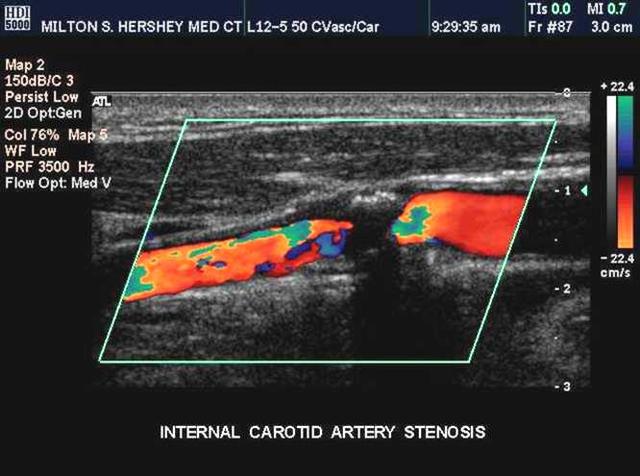

搜检颈动脉,身体搜检可以听诊颈部血管有不有杂音(轻度的狭隘纷歧定有杂音),辅诊搜检初筛是颈动脉超声,无创伤,可以重复,但一般对狭窄病变有些放大(就是说看起来可能比着实的狭窄要老火些);进一步检查可以做颈部血管的磁共振血管造影概略CT颈动脉造影,这两种检查也属于无创,但是需要注射造影剂的;再等于直接插入导管做颈动脉造影。

颈动脉有局促怎么办?严重的虽然要开明。一样平常来说,假定有脑缺血发作的症状大要有了脑梗死,磁共振可能CT颈动脉造影显露70%或以上的窄小、能够直接的血管造影局促在50%或以上,就要手术开通血管了(固然还有别的一些指证)。最经典的手术办法便是后头说过的颈动脉内膜剥脱(切除)术,此刻另有微创的颈动脉支架植入术。各种手术办法都是有各自的顺应证的。